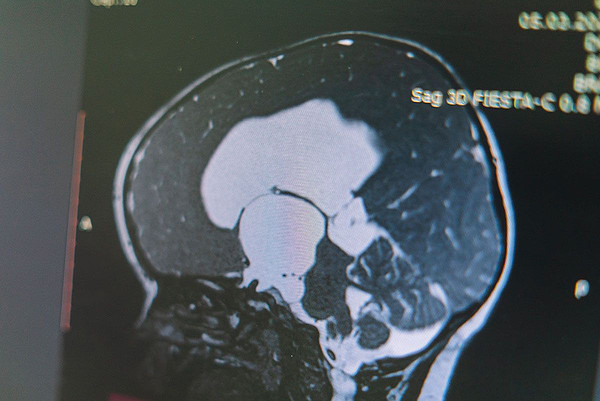

В Кирове сделали сложнейшую операцию на головном мозге 1,5 годовалому малышу 16 декабря 2022 14:18 1 778 Медицина 16 декабря 2022 14:18 1 778 В Кировскую областную детскую клиническую больницу 1,5 годовалый пациент был доставлен с признаками прогрессирующей гидроцефалии.